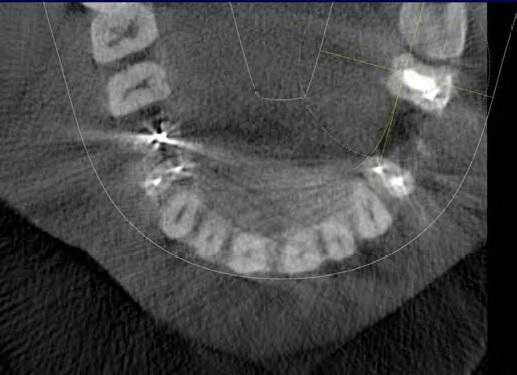

Рис. 1. Асимметричное строение нижнеальвеолярного нерва, добавочный канал в области нижней челюсти справа во фронтальной проекции конусно-лучевой компьютерной томографии от Vatech.

Лучевое обследование проводилось на различных этапах имплантации. Как правило, всем пациентам выполнялась ортопантомография на дооперационном этапе. В сложных клинических ситуациях использовались дентальная объемная томография. Изучение литературных источников по топографической анатомии лицевого скелета показало отсутствие какой-либо информации о связи строения и расположения нижнечелюстного канала с вероятностью повреждения нерва при установке имплантатов. Результаты проведенных собственных рентгеноанатомических исследований челюстно-лицевой системы позволили выделить клинически значимые особенности строения и расположения нижнечелюстного канала и нерва в теле челюсти. В этой связи к предрасполагающим анатомическим факторам риска развития хирургических осложнений при дентальной имплантации могут быть отнесены: